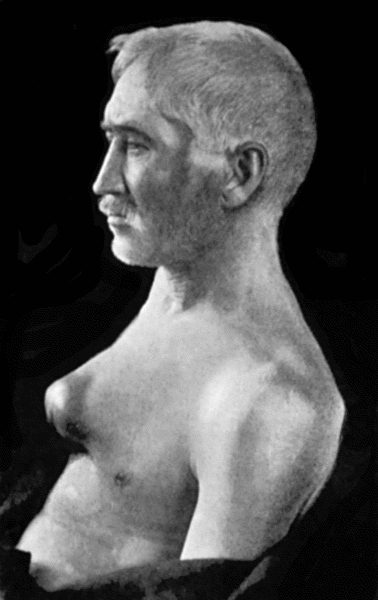

| 74. | Thoracic Aneurysm threatening to rupture | 313 |

| 75. | Innominate Aneurysm in a woman | 315 |